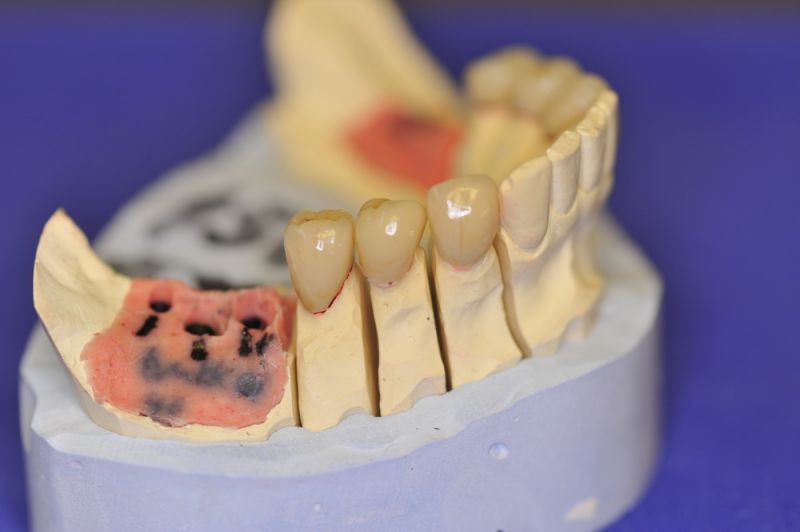

2. Extrem schlechte knöcherne Verhältnisse im Unterkieferseitenzahnbereich, die sich intraoperativ noch einmal als ungünstiger darstellten, als bereits in den Voruntersuchungen erkennbar.

3. Sehr dünne Implantate, die von ursprünglich zwei je Kieferhälfte auf letztendlich drei je Kieferhälfte umgeplant werden mussten.

4. Notwendigkeit die Mundhygienefähigkeit der Arbeit auch unter sehr beengten Verhältnissen zu schaffen, um der Arbeit eine günstige Prognose mitzugeben.